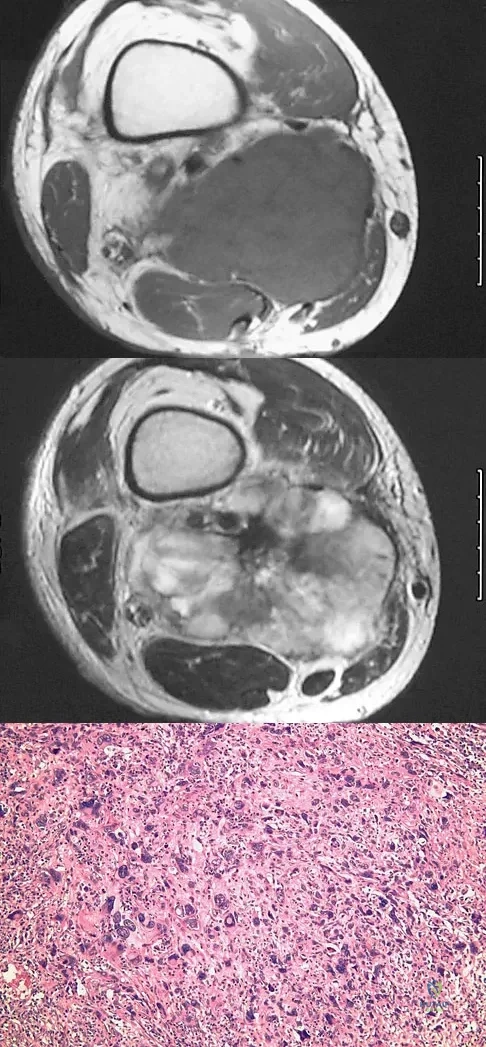

Figures 14a and 14b show the plain radiographs of an 85-year-old woman who has had severe pain in the right knee for the past 4 months. Management should consist of

The patient has osteonecrosis of the lateral femoral condyle with collapse of the articular surface. Because there is already collapse of the articular surface, a total knee arthroplasty is the treatment of choice. The results of total knee arthroplasty in these patients are usually excellent. However, knee replacement is only a resurfacing procedure, and some patients with global osteonecrosis of the distal femur may have residual pain after knee replacement. High tibial osteotomy may be indicated in younger patients who have a varus deformity and localized osteonecrosis. Arthroscopic surgery would provide minimal relief for this patient because there is already collapse of the articular surface. A hinged knee brace will not adequately unload the joint. An osteochondral allograft should be considered only for younger patients with localized osteonecrosis. Bergman NR, Rand JA: Total knee arthroplasty in osteonecrosis. Clin Orthop 1991;273:77-82.